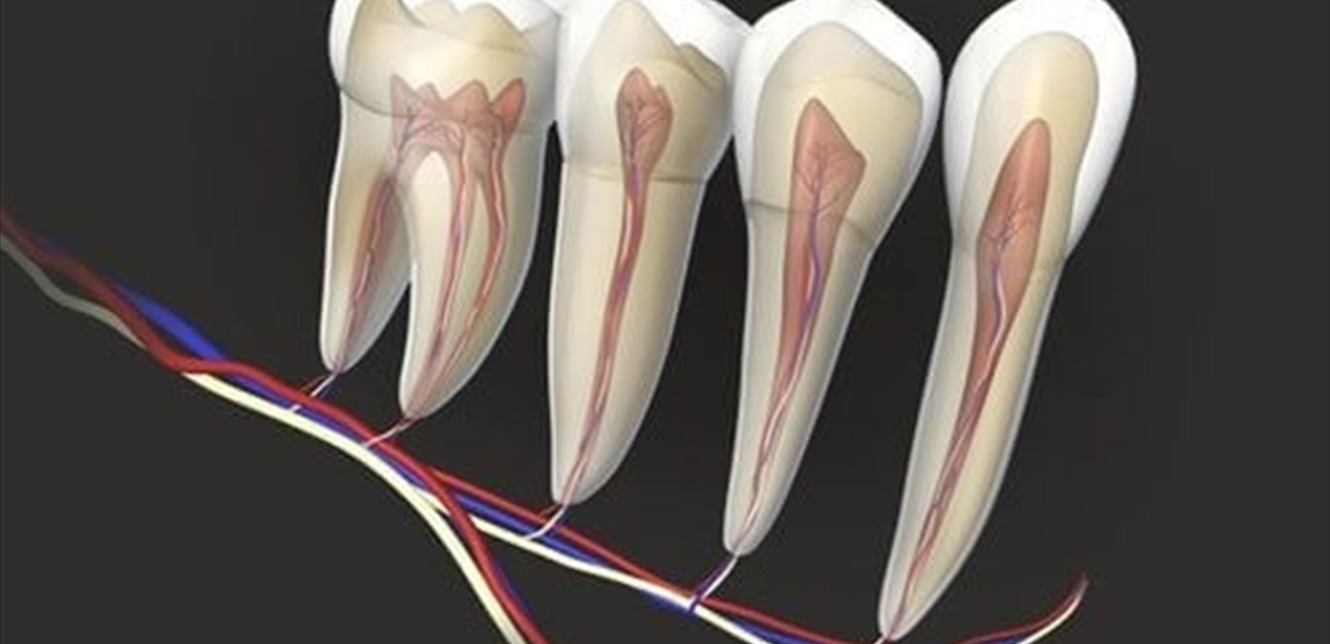

ووفقا لـ”واشنطن بوست” فإن الدراسة، التي نُشرت في مجلة الطب الانتقالي، تابعت 65 مريضًا في معهد طب الأسنان بمستشفى جايز في لندن، خضعوا لعلاج قناة الجذر أو جراحة ما بعد الجذر لإزالة العدوى والالتهاب من الأسنان المصابة. وجمع الباحثون عينات دم في خمس فترات: قبل العلاج، وبعد ثلاثة أشهر، وستة أشهر، وسنة، وسنتين.

ويشير الخبراء إلى أن الالتهابات الفموية قد تسمح للبكتيريا بالدخول إلى مجرى الدم، ما يؤدي إلى التهاب مزمن يساهم في أمراض القلب والسكري وأمراض أخرى. قد تصل هذه الجراثيم أيضًا إلى الرئتين مسببةً التهابات تنفسية، أو إلى صمامات القلب، مما قد يؤدي إلى حالات نادرة وخطيرة مثل التهاب الشغاف.